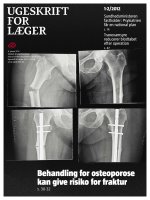

Bisfosfonatbehandling af osteoporose og risikoen for atypiske femurfrakturer Læs mere om Bisfosfonatbehandling af osteoporose og risikoen for atypiske femurfrakturer

Bisfosfonatbehandling som mulig årsag til spontan bilateral atypisk femurfraktur Læs mere om Bisfosfonatbehandling som mulig årsag til spontan bilateral atypisk femurfraktur

Atypisk femurfraktur hos en patient uden bisfosfonatbehandling Læs mere om Atypisk femurfraktur hos en patient uden bisfosfonatbehandling